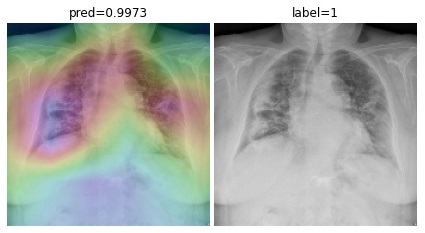

To overcome the aforementioned issues and force the model’s attention to the correct regions of interest (ROIs), we introduce the COVID-CXNet. Our model is initialized with the pretrained weights from CheXNet. A dataset of 3,628 images, 3,200 normal CXRs and 428 COVID-19 CXRs, are divided into 80% as training-set and 20% as test-set. Batch size is set to 16, rather than 32 in previous models, regarding memory constraints. Grad-CAMs of the COVID-CXNet for random images are plotted in Fig. 15.

Figure 15: Grad-CAM visualization of the proposed model over sample cases

More Grad-CAMs are available in Appendix A. Heatmaps are more accurate than previous models, while an accuracy of 99.04% and an f-score of 0.96 are achieved. Table 3 is the confusion matrix of the proposed model.